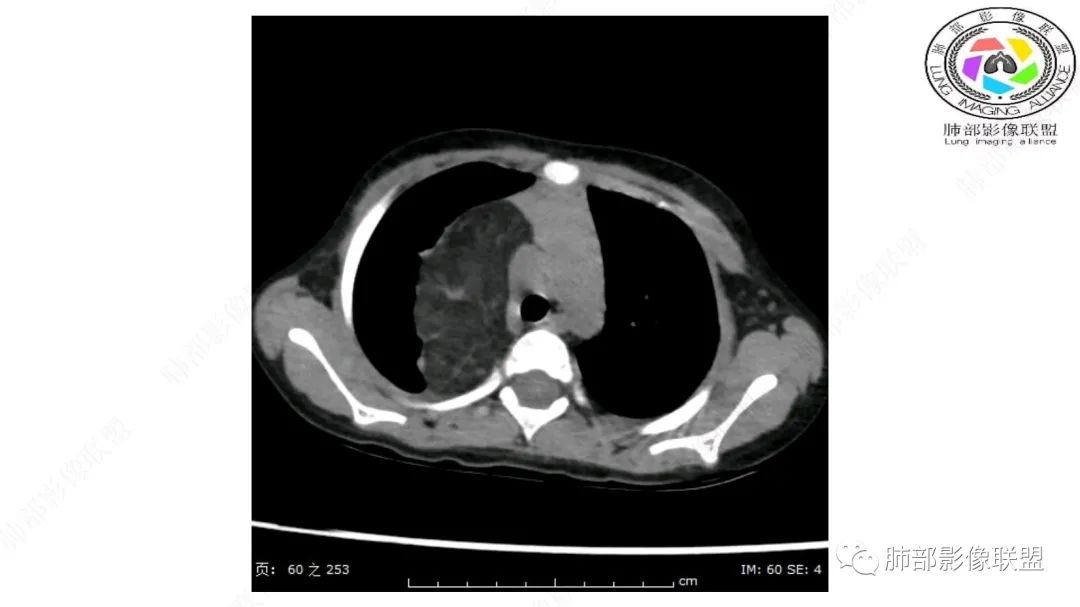

右肺门上方,位于纵隔胸膜旁见巨大肿块,脂肪为主混合密度,内见细小血管影,肿块最大长径与纵隔胸膜平行,包绕右肺上叶肺动脉,右肺上叶及纵隔结构推压,无侵蚀破坏,良性肿瘤,起源纵隔胸膜血管平滑脂脂肪瘤。

跨肺门,包绕肺血管分支,邻近肺组织受压肺不张。

可以看到造影剂进入的丛状结构

密度不均,非纯脂肪成分。斑片状密度略高区域有轻度填充式强化。

婴幼儿,病变较大,跨肺门,分叶,富含纤维或黏液、含成熟脂肪,破坏力弱或无,浸润性生长模式不明显,未见远处转移。

病灶属于交界区,主体位于肺内,占位效应明显,前方突入胸壁,胸腺受压变形,胸膜显示欠清楚;病灶包绕上叶肺动脉;似乎有体动脉供血。符合肺内的点:包绕上叶肺动脉分支;符合纵隔的点:前方似乎突入胸壁,与胸腺关系比较密切,但是与上腔静脉的关系提示病灶不支持纵隔来源,前纵隔的常规会将上腔静脉受压后移、外移,这是不符合的。

手术记录:见右肺上叶肿物,肿物与右肺上叶关系密切。与纵隔无粘连,逐步分离肿物,见肿物大小约6cm*5cm,边界清楚,于右肺上叶粘连,边界清楚,肿物包绕右肺上叶血管及支气管。超声刀逐步游离肿物,完整切除肿物,右肺上叶肺组织无破溃,表面无出血。